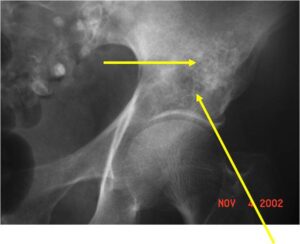

Radiology emulates pathology: Biphasic Tumor

- One region low grade chondrosarcoma

- Second more aggressive area with bone destruction, lysis of calcification, soft tissue mass

- Cortical permeation and a soft tissue mass in 70% of cases

Ill-defined, lytic intraosseous lesion

- Devoid of calcifications in continuity with lesions having the features of a cartilaginous tumor

Characteristically abrupt transition between chondroid tumor and dedifferentiated, lytic component

Bone may be expanded and adjacent cortex thickened